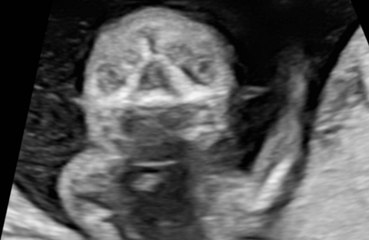

Whitney Port's husband wants their journey to having another child to "be over" following years of struggles.